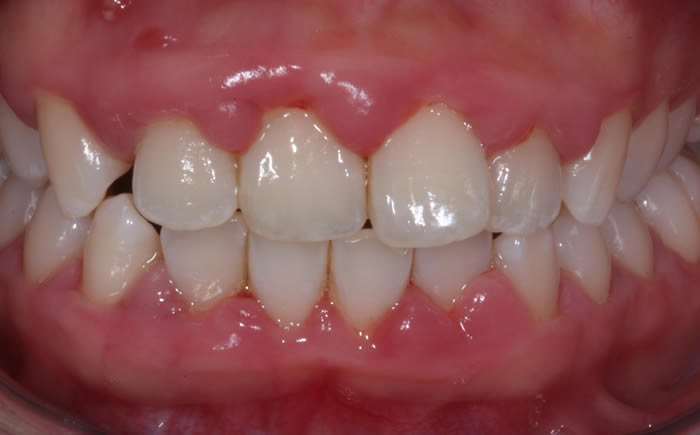

Gum disease

Case One (2 images)

Treatment of severe gum disease.

Case Two (2 images)

Treatment of moderate gum disease.

Case Three (2 images)